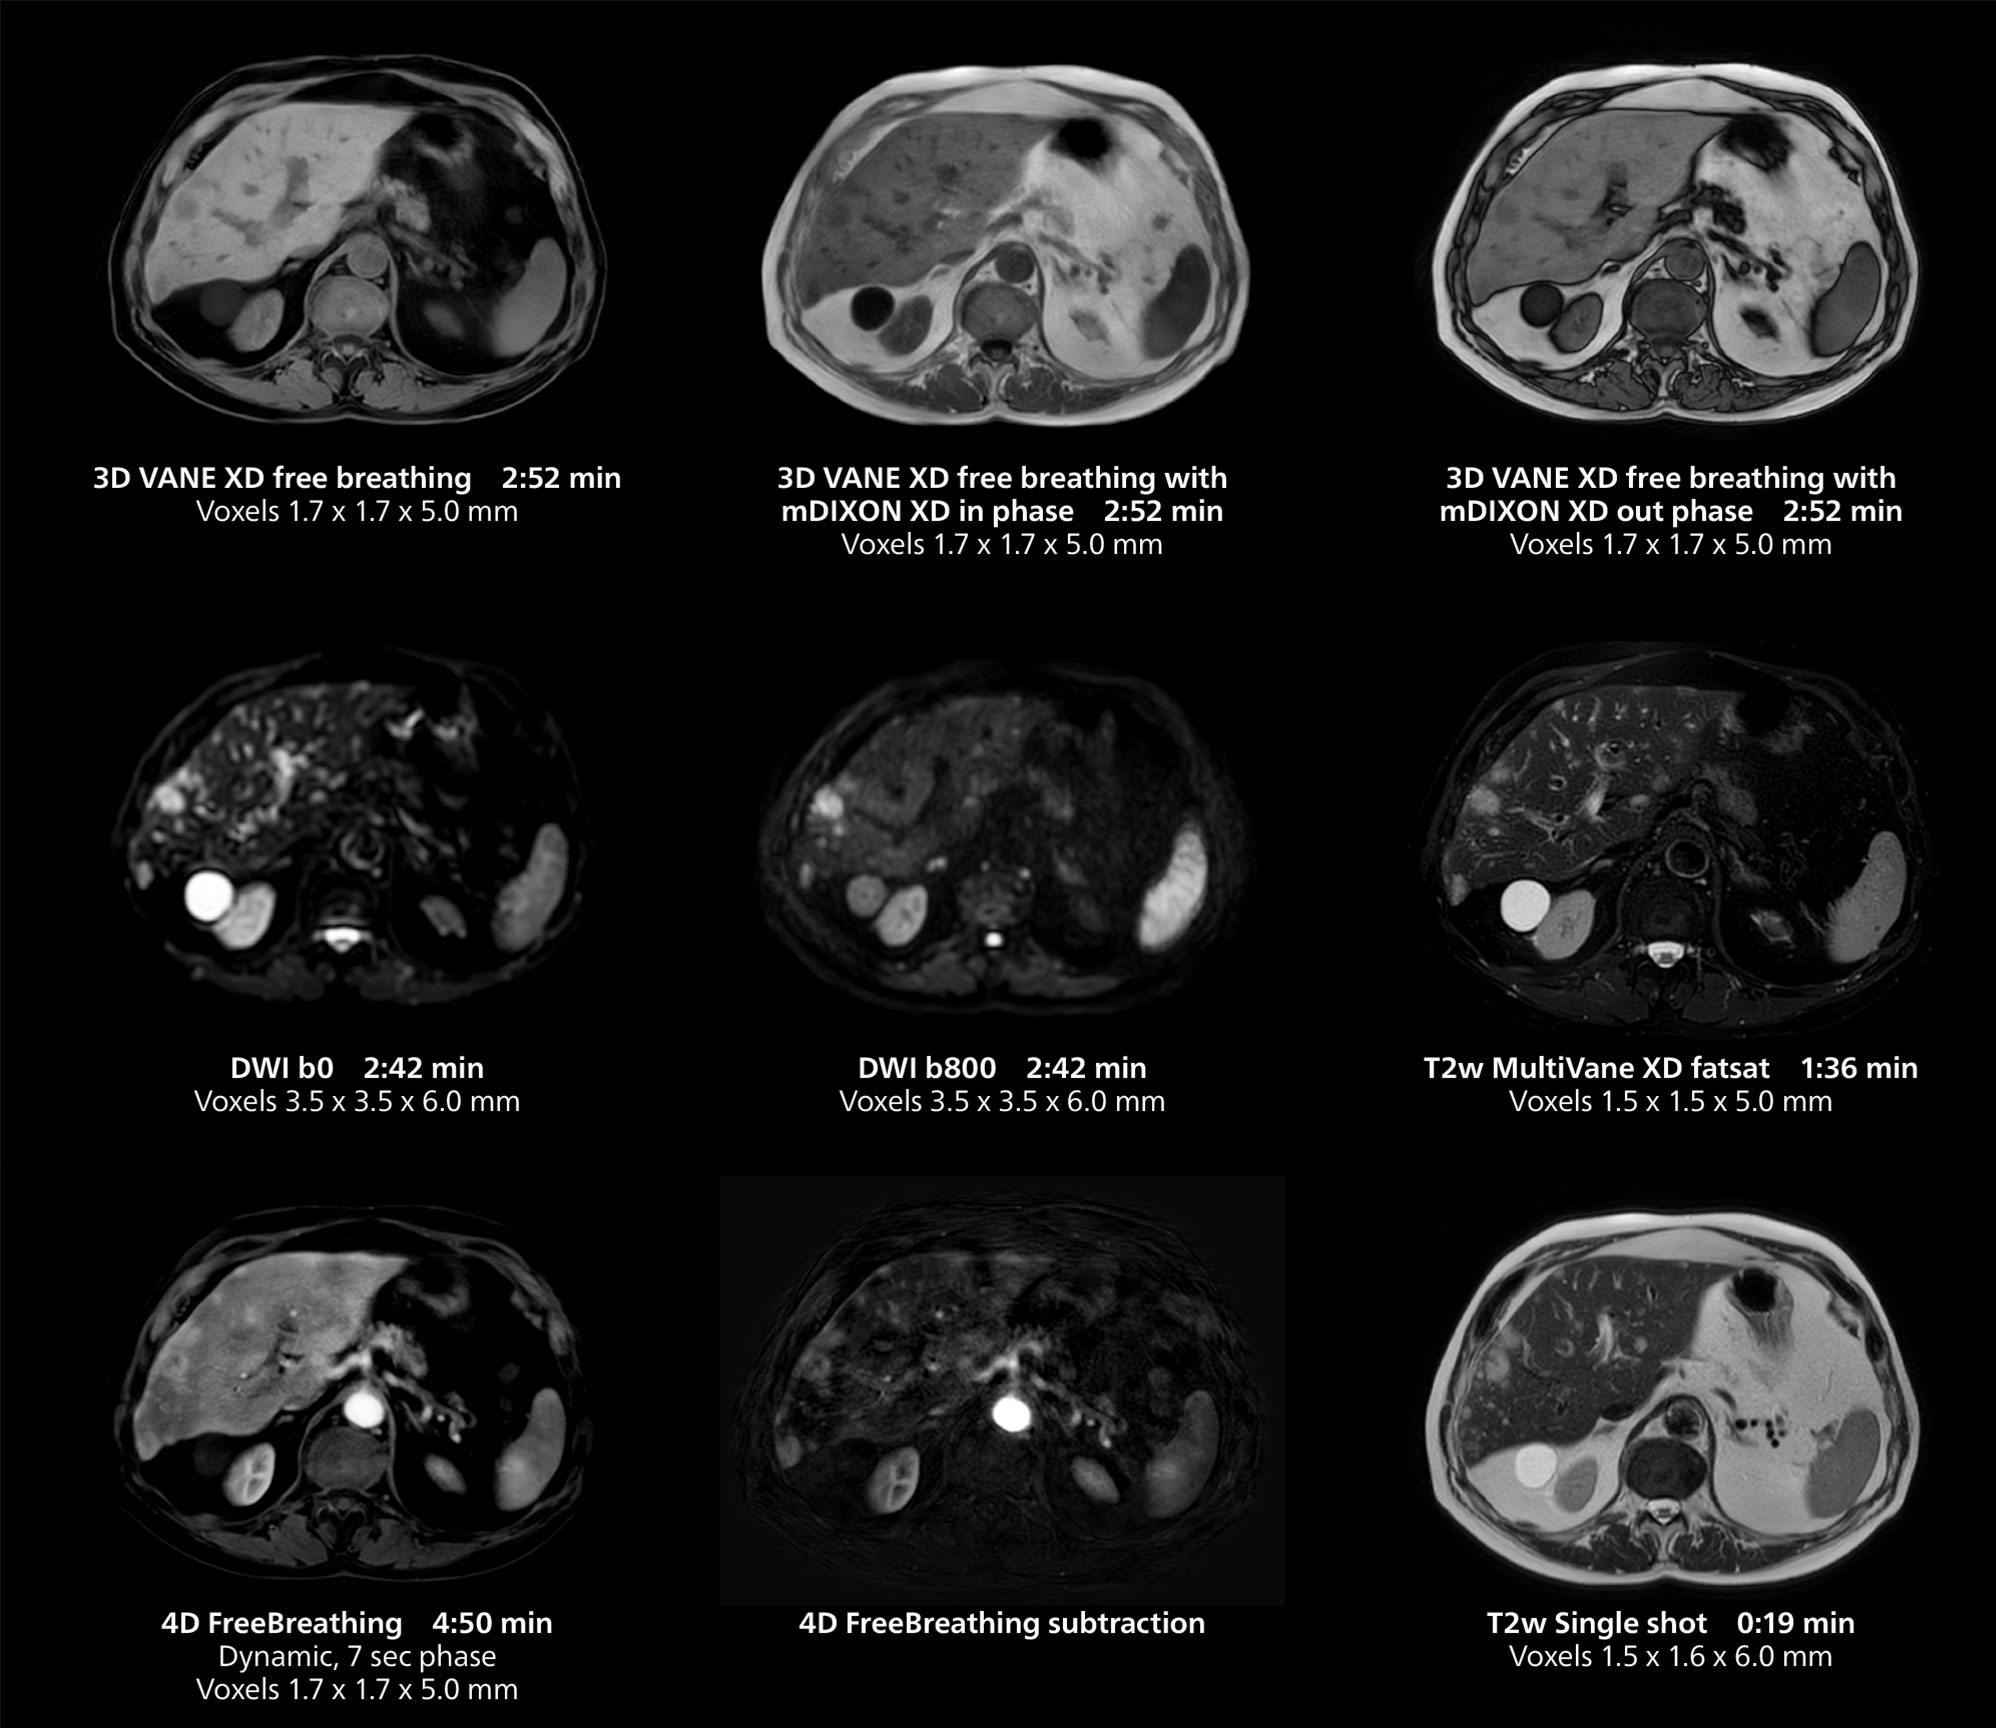

Dr. Gellée highlights the robust free-breathing scans as “the feature that makes the biggest difference in my daily work. The 3D free breathing sequences are very reproducible, and the axial acquisition is very good. For example, in endometriosis, which is one of my focus areas, it provides high contrast and good resolution so that I can see small details. We also use free breathing for liver and pancreas imaging. In multi-phase liver studies, 4D Free Breathing delivers 3-second temporal resolution, making a dynamic scan with more than one arterial phase possible.”

She also uses free breathing with 3D mDIXON to obtain in-phase, water and fat images in a single scan. “It is very reproducible before and after gadolinium, which makes it useful for liver imaging,” she adds.

This case includes 3D free breathing and 4D dynamic free breathing MRI of a metastasized liver. A high quality fatsat sequence with good resolution is obtained in 1:36 minutes with T2-weighted MultiVane XD.